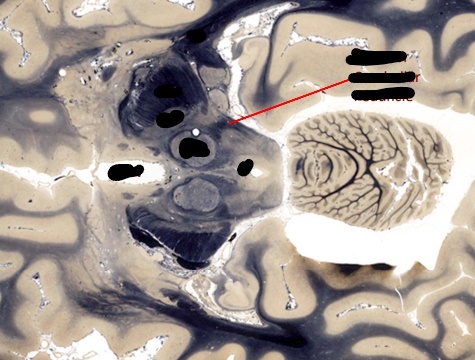

label, note important features

what structures form the walls of the 4th ventricle?

what is the vermis?

discuss the relationship of the vermis with the 4th ventricle?

what portion of the cerebellum contain the deep cerebellar nuclei?

which of these nuclei is normally visible?